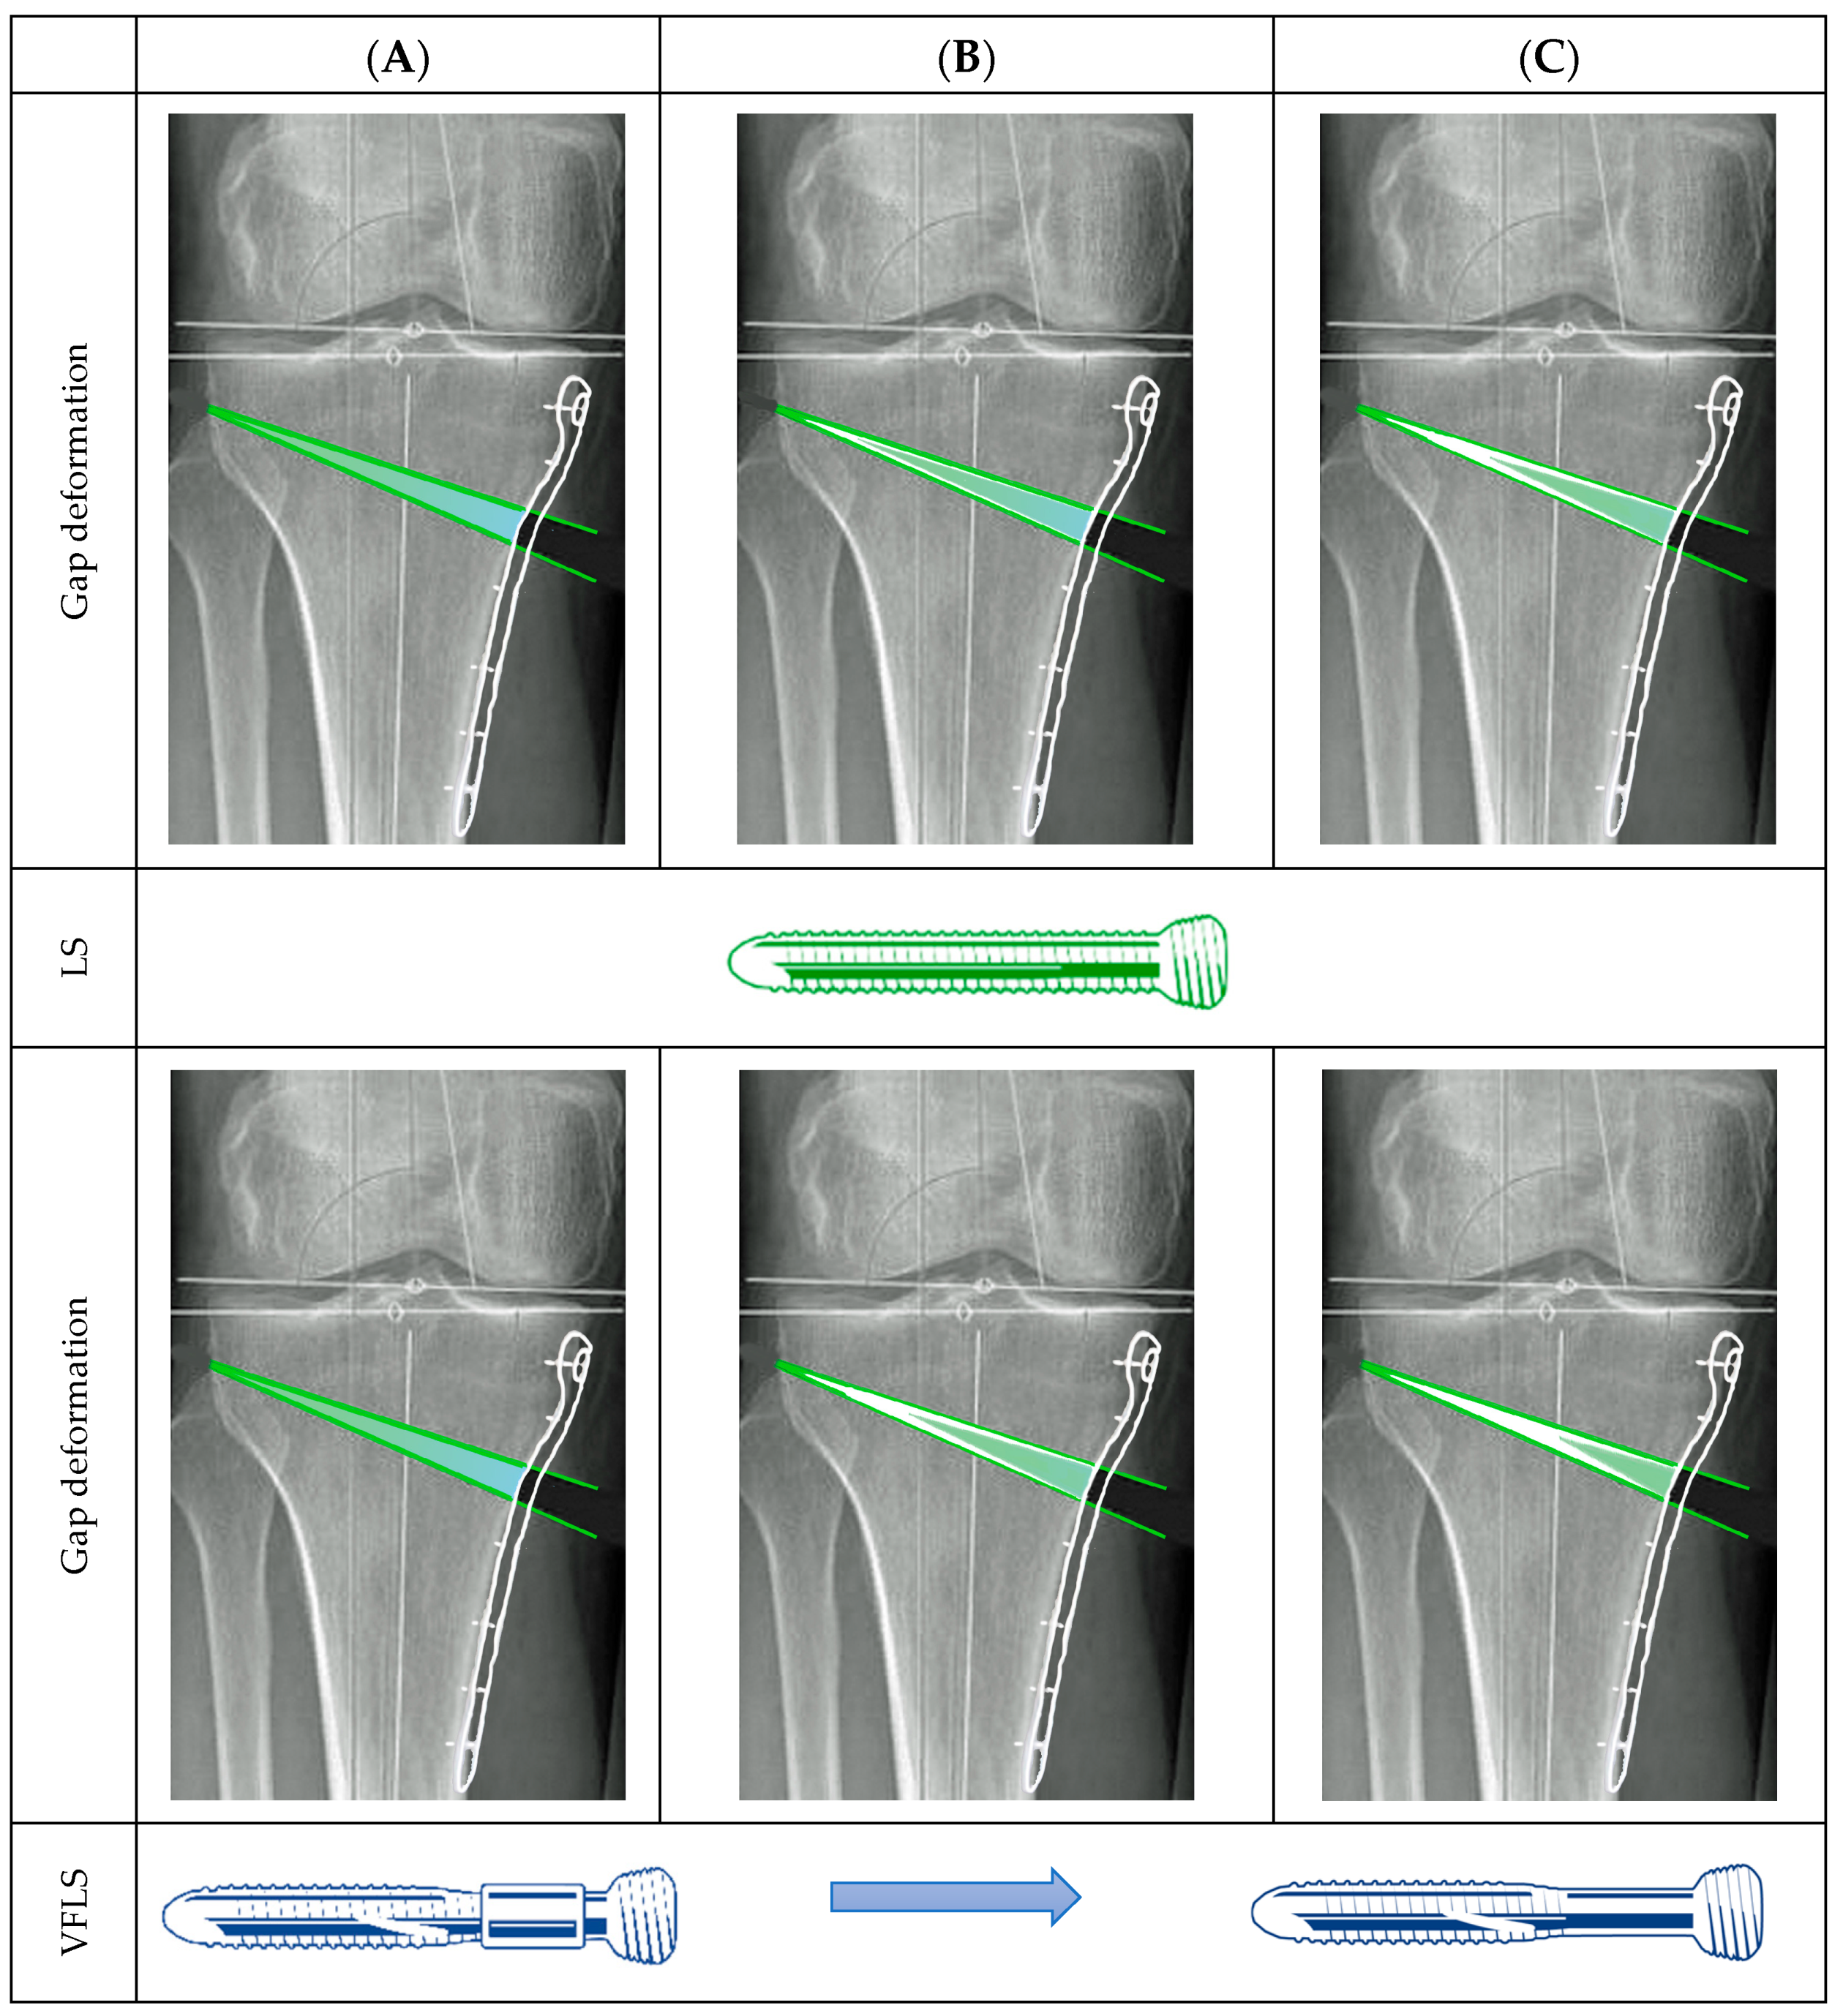

The wedge-shaped osteotomy serves as an interesting and robust model for studying the biomechanical effects of progressive dynamization during bone healing (Figure 3). This model provides a unique opportunity to evaluate differential mechanical influences within the same individual across various gap dimensions. Specifically, it allows for the examination of the healing response in a small lateral gap near the hinge, a larger medial gap adjacent to the medial cortex, and the range of intermediate gap dimensions in between. When standard locking screws are employed, weight-bearing forces result in a significant strain on the lateral, extremely small, portion of the osteotomy gap. In contrast, the medial portion, situated under the fixation plate, experiences a progressively diminishing strain during the healing process as the consolidation of the lateral and middle portion progress. This uneven distribution of mechanical strain can lead to delayed or incomplete closure of the medial gap, as the reduced strain stimulus often fails to reach the threshold required for initiating and concluding bone regeneration. In contrast, the use of devices based on the Variable Fixation concept introduces a mechanism of controlled strain increase over time. The initial stability, followed by the gradual decrease in construct rigidity, increases the chances to reach the strain environment, falling within the range that stimulates osteogenic activity along the entire fracture gap. As a result, the likelihood of uniform bone deposition across the entire fracture gap increases, promoting more effective consolidation of the osteotomy.

Figure 3.

This image illustrates the expected strain distribution within the osteotomy gap. Green areas indicate where the strain is expected to support new bone formation, while light-blue areas show strain levels that are likely too low to promote bone apposition (white). (A) Initial strain conditions at the start of treatment using both standard locking screws (LSs) and Variable Fixation Locking Screws (VFLSs). Strain levels with LS fixation decrease over time, potentially leaving parts of the gap unfilled for extended periods. (B,C) As the degradable sleeve of the VFLS resorbs, gap strain conditions evolve, progressively increasing the likelihood of reaching strain levels conducive to bone formation throughout the entire gap.